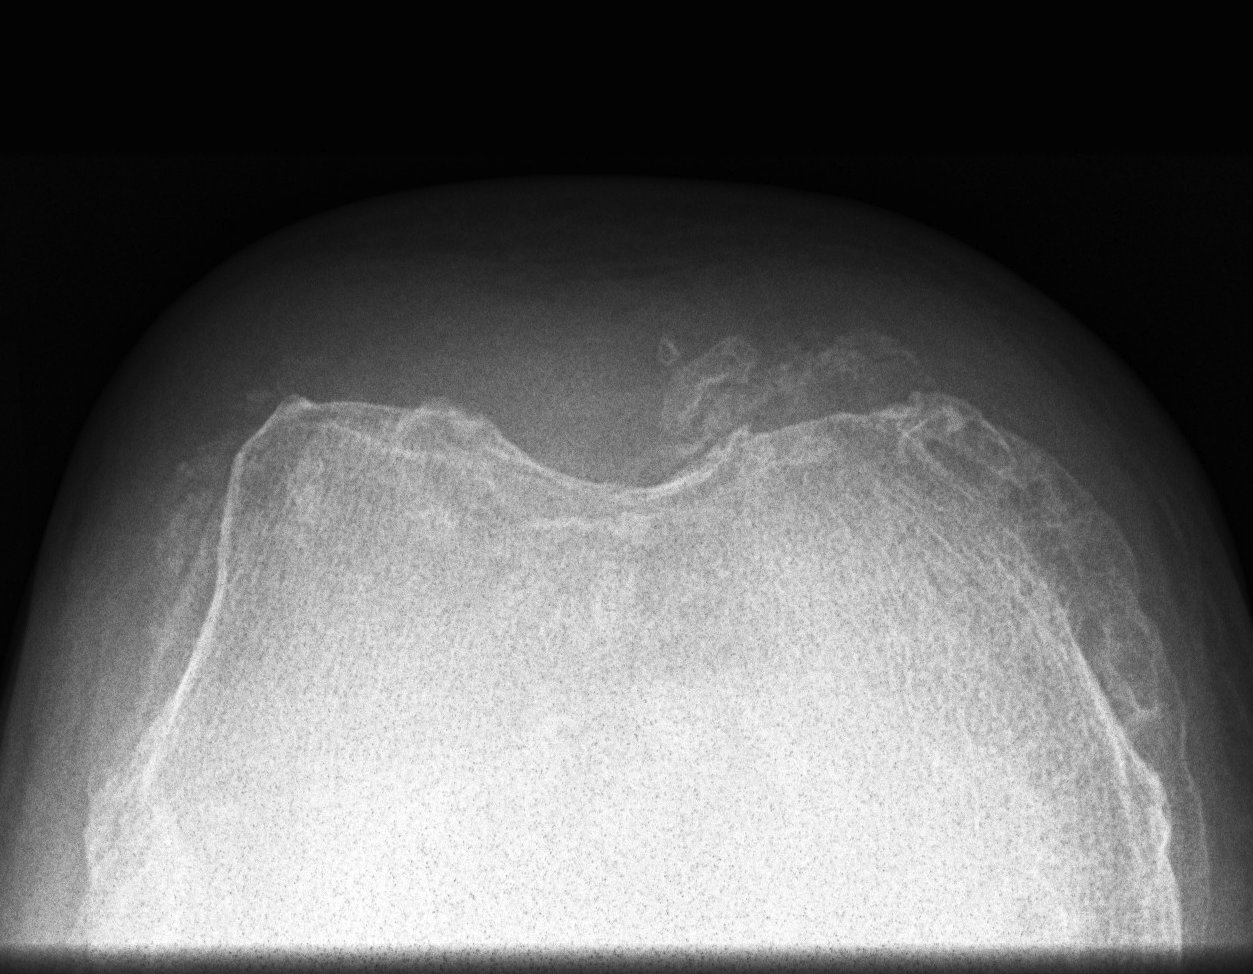

X-ray

Narrowing / osteophytes / sclerosis

Tilt / subluxation

Tilt Subluxation / osteophytes